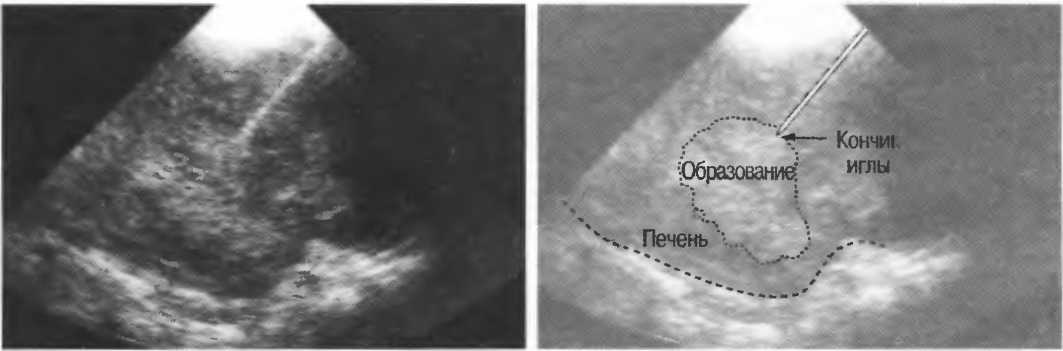

На практике, наиболее значимые в клиническом плане артефакты возникают при проведении биопсии или аспирации под контролем ультразвука. До тех пор пока кончик иглы не появится в плоскости сканирования на экране, он не будет визуализироваться, и может создаться ложное представление о том, что игла значительно короче (рис. 21в).

Рис.21 в. Изображение иглы в емкости с водой. Слева игла находится в плоскости сканирования не полностью, в результате чего выглядит короче, чем есть на самом деле (крестик определяет реальную глубину проникновения иглы). Справа игла визуализируется полностью.